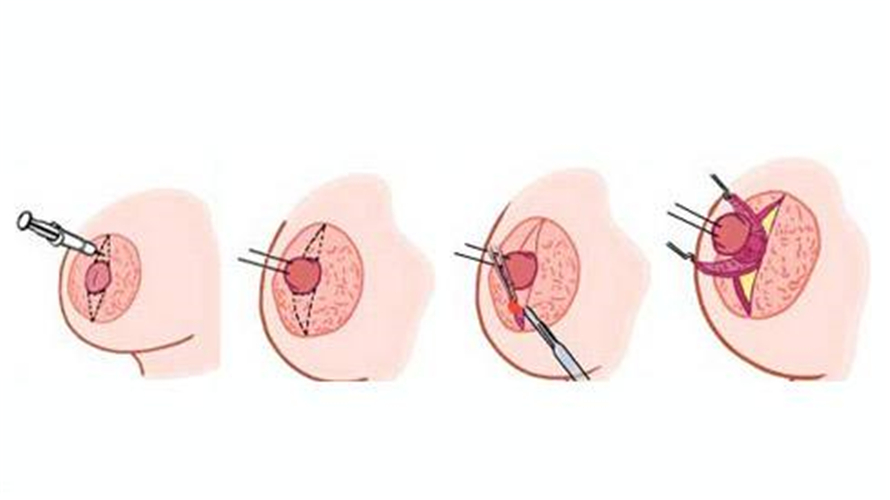

A:想要解決乳頭內陷,為避免誘發乳腺炎等疾病,建議儘早行手術治療。通過手術的方式,將患者的乳頭環狀括約肌切開,然後重新進行縫合矯正。在手術中應注意保護好患者的乳腺導管,效果一般較好。若患者有手術的相關禁忌症或不願意進行手術,也可進行局部乳頭……